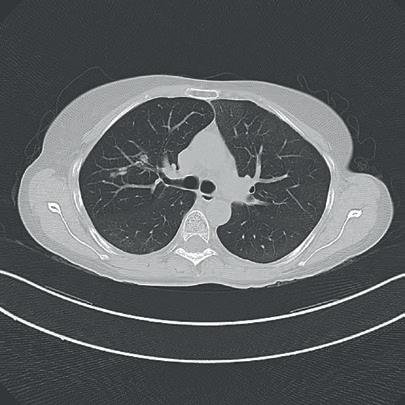

The incidence of lung cancer has increased considerably in the last few decades with the lung as the most common site of metastatic involvement. Despite the improvements in the diagnosis and treatment for malignant lung tumours, the prognosis of the patients is still unsatisfactory.1 Currently, locoregional chemotherapeutic techniques such as transpulmonary chemoembolization (TPCE) for the treatment of lung malignancies have gained increasing importance. The purpose of this retrospective study was to evaluate local tumour response and patient survival after the treatment of pulmonary metastases using TPCE as a palliative treatment method.

In TPCE, a 5 French (Fr) endovascular sheath and 5Fr headhunter catheter are routinely placed transfemorally under fluoroscopy until the pulmonary artery and subsequently the tumourfeeding segmental pulmonary branch are reached. A balloon catheter (up to 7mm in diameter) is optionally placed for better results.2 This selective pulmonary artery catheterisation results in a blockage of the arterial supply to the tumour tissue, resulting in regional ischaemic necrosis in the target tumour tissues while reducing damage to the surrounding normal lung parenchyma. Thereafter, mitomycin

and gemcitabine as chemotherapeutic agents are administered in combination with an embolization of lipiodol and microspheres. This extends the storage time of the injected cytostatics in the tumours and reduces the outflow into

the circulatory system.3 Consequently, the frequency and severity of systemic effects are limited. Other occlusion materials used are coils, polyvinyl alcohol, degradable starch microspheres, and gelatin sponges.

In our study, 223 patients (138 women, 85 men; mean age: 59.3±11.9 years) with unresectable lung metastases and/or not responding to systemic chemotherapy received repetitive TPCE (mean number of sessions 4.7±3.7) between January 1990 and May 2021. Patients had predominant lung metastases and in most cases with bilateral lung involvement. Origin of the metastases were either colorectal carcinoma (n=139) or breast cancer (n=84). Tumour-supplying vessels were catheterised selectively in order to apply chemotherapeutic agents locally, combined with lipiodol and microspheres. The response was assessed according to the revised RECIST criteria.

Of the evaluated 183 cases, partial response was achieved in 4.9% (n=9), stable disease in 62.3% (n=114), and progressive disease in 32.8% (n=60) of the patients. Mean and median overall survival time were 23.5 and 14 months, respectively.

TPCE can be used as a palliative treatment in unresectable lung malignancies to reduce the tumour burden or to achieve local tumour control,4 or as a neoadjuvant or curative treatment option combined with thermal ablation such as radiofrequency ablation (RFA) and microwave ablation (MWA) (Figure 1).5,6